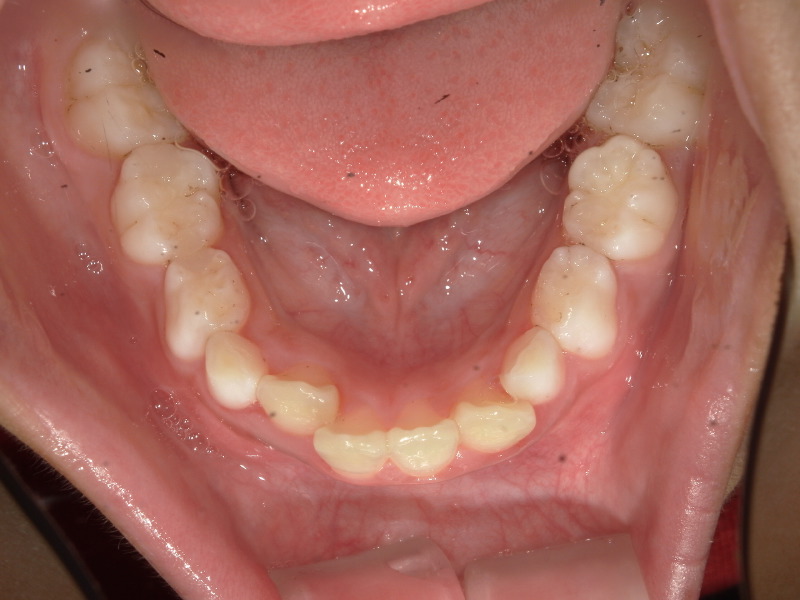

最初の検査時に撮影した写真です。

下の歯並びは2番目の歯が後ろから生えてきており、スペースが足りないようでした。